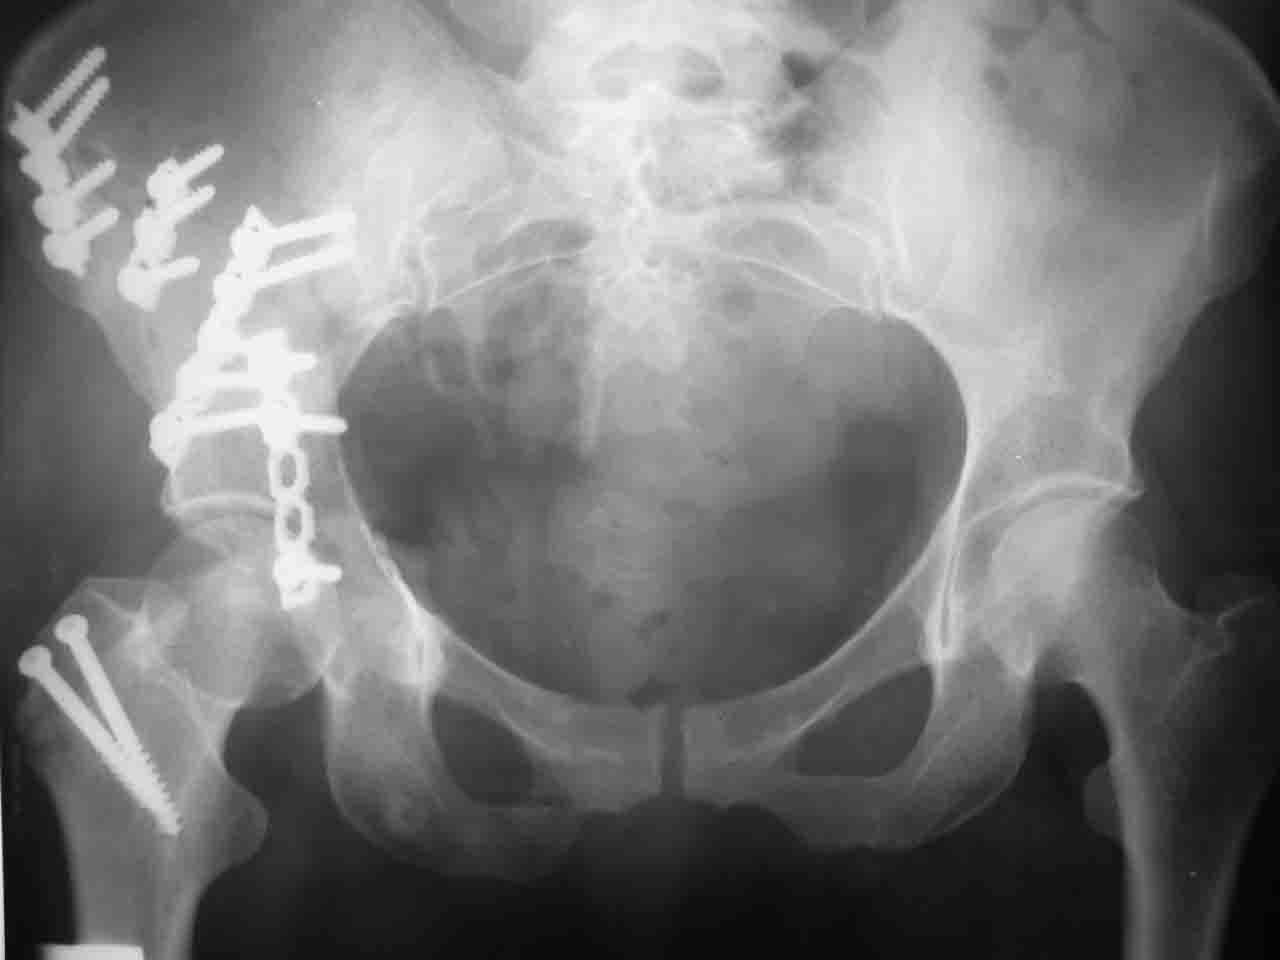

Интерес к реконструкции вертлужной впадины у меня появился довольно-таки давно, но до недавнего времени как-то не ощущалась готовность к практической реализации, а местный подход достаточно консервативен - перелом срастется,

а далее будет видно. Такую точку зрения я не разделяю, поэтому через конференции,ортофорум и свои случаи пытаюсь практически и теоретически *продвинуть* для себя тему реконструкции вертлужной впадины.

Логика подсказывает, что все-таки лучше иметь анатомически полноценную впадину, хотя ранее упоминалось состояние вторичной конгруэнтности и одно наблюдение у меня есть, когда у больного с полностью нарушенной анатомией впадины и подвывихом головки бедра кзади и кверху боли отсутствовали при относительно достаточном для стиля жизни больного объёме движений. Но это только одно наблюдение и кроме перелома впадины у этогобольного была и тяжелая ЧМТ в анамнезе. Основываясь на формулировке структуры ацетабулюм Э. Летурнеля - как перевернутой буквы Y, впадина для полноценной функции сустава должна иметь сферичность, соответствующую размеру головки бедра и если один из компонентов в дефиците, то функциональные последствия рано или поздно проявятся.

Сложностью, ассоциативностью характера перелома, я бы с радостью воспользовался мининвазивной перкутанной фиксацией винтами, но боюсь, что результат был бы ещё хуже, техникой непрямой репозиции перелома не владею, поэтому пытаясь получить анатомичную впадину приходится широко открывать, по крайней мере пока, а дальше буду пытаться уменьшать пространство...

Илеофеморальный доступ не совсем передний и сравнительно с илеоингвинальным, и Кохера-Лангенбека открывает весь наружный таз кроме самых передних отделов лонных костей, фиксацию которых я не ставил в задачу. Обширность диссекции, большая длительность операции и более высокий риск гетерооссификации - отрицательные моменты в обмен на возможность легче ориентироваться.

Комбинированные доступы - хорошая альтернатива, меньший процент осложнений, но я заметил , что без сбора *мозаики* безымянной кости сложно отрепонировать переднюю колонну, а с нерепонированной передней колонной невозможно анатомично собрать заднюю колонну и соотв. фрагменты стенки - так.что все равно открывать придется широко. Поэтому выбирая комбинированный

подход, передний доступ должен был бы быть продлен до задней трети крыла безымянной кости, а задний - практически до того же уровня, оставляя 6-7 см мостик. При этом вместо одного послеоп. рубца у больного остаются два сравнительно длинных.

Вопрос доступа к вертлужной впадине при остеосинтезе задача не простая. Конечно, у Летурнеля и Тайла всё давно описано, нам остается только брать на вооружение. Но сами понимаете, что не бывает двух одинаковых ситуаций, поэтому в каждом случае вопрос решается сугубо индивидуально. Наша главная цель - восстановить анатомию с нанесением минимальной дополнительной травмы тазобедреннному суставу, думаю с этим никто не поспорит. Расширенный илиофеморальный доступ уж слишком травматичен (как сказал один коллега "таз лежит отдельно, больной отдельно").Стоит ли делать из пациента анатомический препарат для того чтобы легче ориентироваться. Да и нужно ли собирать всю "мозаику"? Мы применяли при таких операциях своеобразную операционную хитрость - сначала устраняли грубое смещение крыла под гребнем с фиксацией так называемой "плавающей" пластиной (временно фиксированной на двух винтах)- доступ или продлевали боковой, или делали небольшой дополнительный разрез над гребнем. Это позволяло устранить грубое смещение и захождение отломков тела повздошной кости, что значительно облегчало репозицию и остеосинтез впадины над сводом. Основное внимание конечно же уделяли нагружаемому задне-верхнему отделу. Сообщите ваш адрес, пришлю схемы и рентгенограммы.